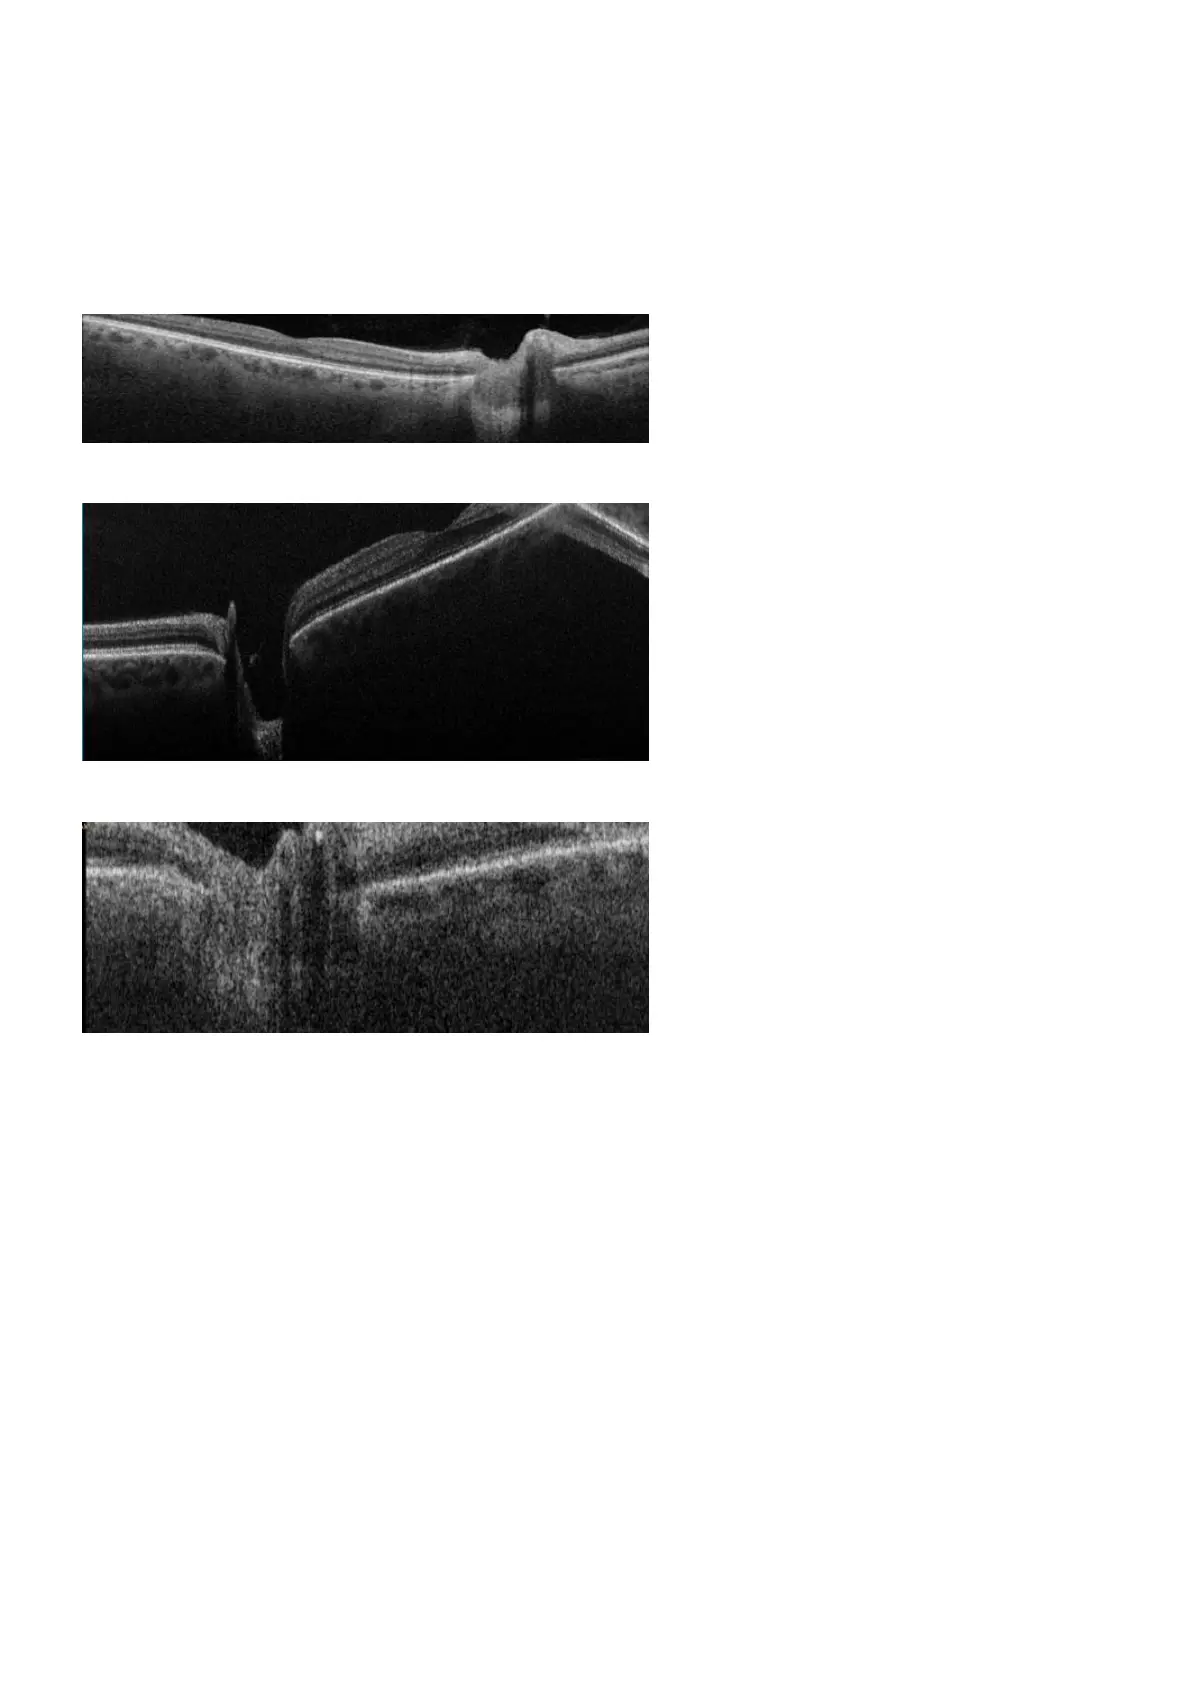

4.9.4 Artifacts - Clipping

You must ensure that the live scan view properly shows the patient's retina. If the retina is too high or too

low the scan may clip the retina and some retinal data may be missing from the scan. The image should be

recaptured if the clipping is significant, or if it affects the scan of the fovea or optics disc. Clipping can be

ignored if it does not affect important structures such as the fovea or optic disc.

FIGURE 19: Example of clipped B-Scan.

FIGURE 20: Example of clipping near the fovea.

FIGURE 21: Example of clipping near the optic disc.